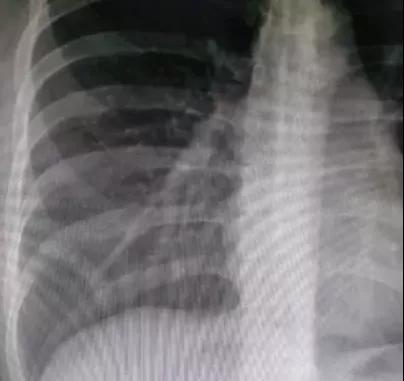

吸气、呼气时胸片影像的差别